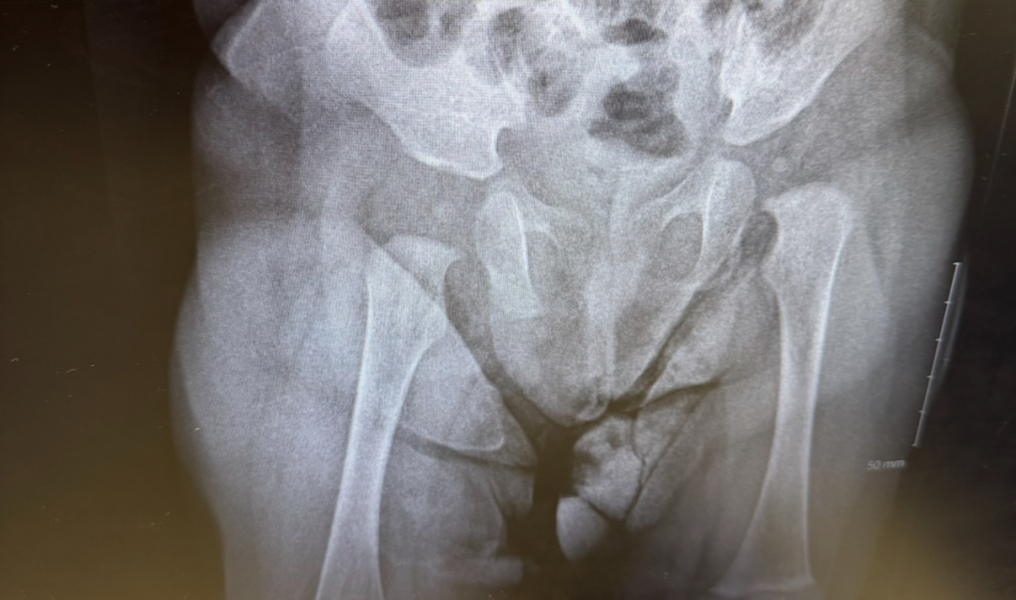

I was obviously concerned though so I took her to see a private consultant who did an x ray. Private consultant said that her x ray looks normal and leg bones measure the same. The only reason for the consultant why her legs appear different could be obliquity of the pelvis. Indeed on the x ray her left hip seems higher than right.